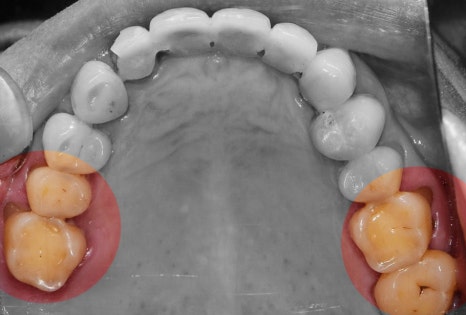

더서울치과는, 석고모델링을 진행하질 않고

구강 스캐너로 인상 채득을 진행합니다.

아울러, cone beam CT 와 해당 데이터를

머징시키게 되면

이런 데이터들을 얻어 낼 수 있는거죠.

Implant fixture 들이 심겨지는 치조골의

여러가지 정보들을 한 눈에 습득을 할 수 있기

때문에 술자의 입장에서는 조금 더 객관적인

진단이 가능합니다.

그래서 이렇게, 미리 사진 예상 식립위치를

결정 한 다음에는